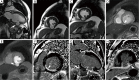

Overview of left ventricular outpouchings on cardiac magnetic resonance imaging

Left ventricular outpouchings commonly include aneurysm, pseudoaneurysm, and diverticulum and are now being increasingly detected on imaging. Distinction between these entities is of prime importance to guide proper management as outcomes for these entities differ substantially. Chest radiograph is usually nonspecific in their diagnosis. Echocardiography, multi-detector computed tomography evaluation and angiography are helpful in the diagnosis with their inherit limitations. Cardiac magnetic resonance imaging (MRI) is emerging as a very useful tool that allows simultaneous anatomical and functional evaluation along with tissue characterization, which has diagnostic, theraputic and prognostic implications. This article gives an overview of left ventricular outpouchings with special emphasis on their differentiation using cardiac MRI.

Keywords: Diverticulum; aneurysm; magnetic resonance imaging (MRI); pseudoaneurysm.